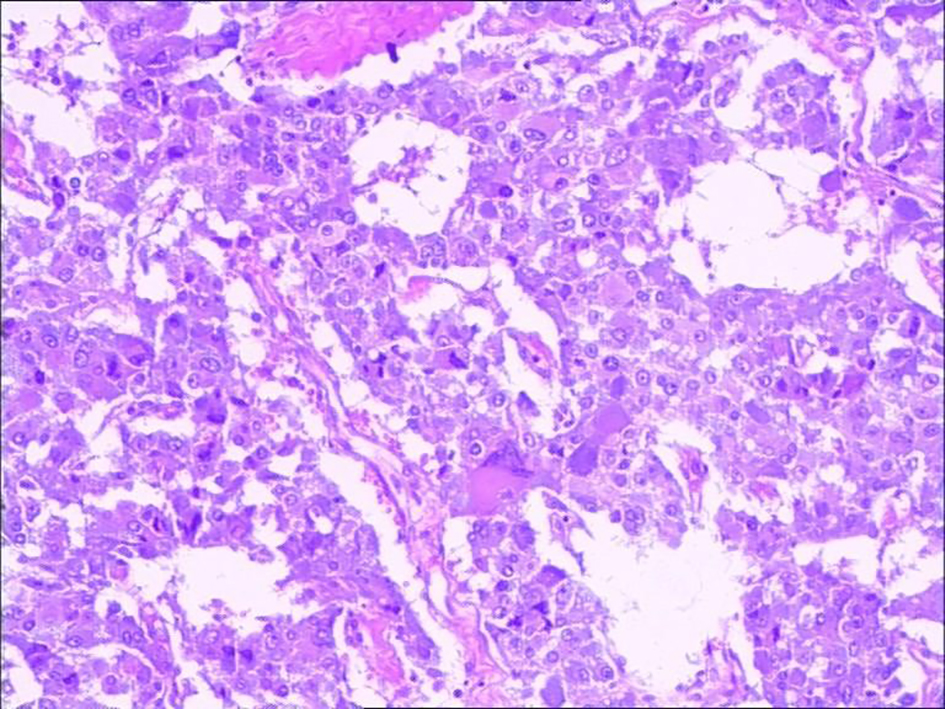

To make firm diagnosis, a decision was made to carry out retroperitoneal mass biopsy with ultrasound guidance under monitored anesthesia care (MAC). The punch biopsy was carried out successfully. During the procedure, the maximum blood pressure was up to 178/101 mm Hg and patient felt no discomfort. Pathological examination showed the following: morphologically consistent with pheochromocytoma, immunohistochemically cytokeratin (-), CgA (+), Syn (+), S-100 (+), and Ki-67 (+ about 1%) (Fig. 2). Through multidisciplinary MDT (Department of Vascular Surgery, Anesthesiology, Urology, Ultrasound Intervention, Infectious Diseases, Endocrinology, Intensive Care Unit), a collective diagnosis of ectopic (abdominal aorta) pheochromocytoma was made. The patient was given persral administration of phenoxybenzamine 10 mg bid, metoprolol tablets 25 mg bid, nifedipine controlled release tablets 32 mg qd, 3 weeks before the surgery until to the day of surgery. Six days prior to surgery, in addition to normal diet, the patient received 1,000 mL sodium lactate Ringer solution, 500 mL converted sugar sodium chloride solution for expansion per day. Patient’s blood pressure was contributed at 135 - 110 and 75 - 90 mm Hg.

![]() Click for large image | Figure 2. Eccentric nuclei large cell is shown by basophil included. Immunohistochemistry shows CgA (+), Syn (+). |

Pathological examination revealed that the tumor was large in size, 20 × 14 × 5 cm (Fig. 4). The capsule was intact, part of which was affected by the tumor. A proportion of tumor cells showed signs of fast growing with nuclear mitosis at 3/50 HPF. The pathological diagnosis was pheochromocytoma; immunohistochemistry showed CgA (+), Syn (+), S-100 (+), Ki-67 (+ about 1%). The patient was cured and discharged on the 10th day after surgery with no complications.